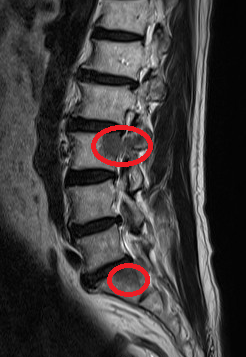

まず、①腰椎圧迫骨折について。これは転倒や尻もちなどのケガで起

やっかいなのは、このタイプの骨折が「普通の腰痛」と非常によく

亀背変形

がんの骨転移

圧迫骨折であれば、早期に治療を始めることで亀背変形を最小限に